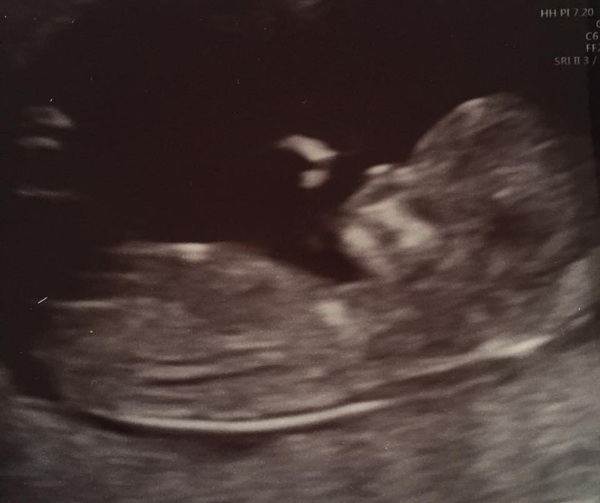

Love all those beautiful scan photos! Grin

Loving all the scan news! I've already signed up for NCT - starts on 12 Dec and there are about 5 sessions I think. Pricey, but we're really keen for information, and I'd love to make friends.

Huge congrats to everyone on their lovely scans, and a special mention to evergreen - I've been keeping everything crossed for you. Best of luck on your big day tomorrow xx

Eek, more gorgeous scan pictures! I'm lurking on this thread but not posting much. Simply coz I get interrupted a lot when I try! I've name changed BTW (old username Theresa) so I will pop my scan on again, you know, just to show I'm really one of the gang. Not just to show off my gorgeous baba again or anything Grin

Yay! Lots of great scan news today :-) congratulations everyone....hope you're now in full bridal prep mode evergreen!

Lovely scans everyone! Really good to see all these little February babies Smile